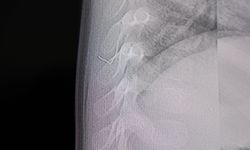

Kadın Hastalıkları, Doğum ve Tüp Bebek Uzmanı Prof. Dr. Murat Bakacak ise MRKH sendromu ve uyguladıkları ameliyatla ilgili şunları söyledi: "MRKH sendromu, doğuştan vajina ve rahmin olmamasıyla seyreder. Bu hastalık genellikle ilk adet döneminde ortaya çıkar. Rahim ve vajinaları olmadığı için hastalar adet göremez ve gebe kalamazlar. Biz bu hastamıza yıllardan beri Fatih hocamla birlikte farklı vajinal oluşturma ameliyatları yaptık. Son olarak tamamen kapalı yöntemle, kalın bağırsağın bir kısmını kullanarak neovajina oluşturduk. Bu ameliyat yaptığımız tekniği diğerlerinden biraz daha fonksiyonel ve faydalı olduğunu düşünüyoruz. İyileşme dönemi nispeten daha rahat ve cinsel fonksiyonlara kavuşmaları çok daha çabuk oluyor" diye konuştu.

Kahramanmaraş’ta doğuştan rahmi ve vajinası olmayan kadınlar için umut veren operasyon yapıldı. Ameliyata alınan kadın hastada sigmoid vajinoplasti ameliyatı ile yeni vajina oluşturularak cinsel fonksiyon kısa sürede kazandırıldı.